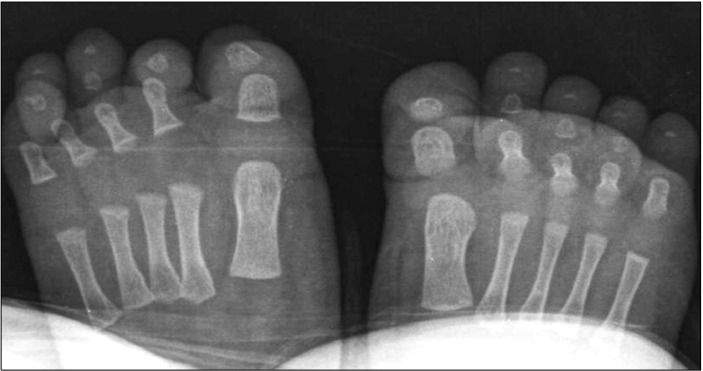

图2:放射检查未发现任何骨骼或软组织异常。

第四脚趾的弯曲先天性指甲基检测如何帮助区分症状相似的疾病: 来自重庆市市辖区江津区中山镇的倪惠君(化名)在浙江省人民医院浙江省立医院被医生诊断为第四脚趾的弯曲先天性指甲。查阅《Dermato-Endocrinology》,第四脚趾的弯曲先天性指甲的出现有多种原因,其中一个重要的原因是基因突变,这需要通过基因检测来明确。基因突变引起的可能会遗传。一名3个月大的倪惠君男孩出现了第四个脚趾甲的指甲畸形。他的左脚第四趾甲与末节指骨不平行,右脚趾甲呈弯曲状(图1A、B)。这两种情况都是出生后观察到的。他没有家族史或可疑的既往史,例如创伤。未观察到伴随的异常。双脚的放射检查显示没有骨畸形或软组织缺损(图2)。基因检测结合临床诊断他的左脚第四趾甲为先天性排列不良,右脚为先天性弯曲指甲。计划定期随访,以防止永久性畸形和并发症。先天性排列不良被定义为与远节指骨纵轴相比,甲基质水平偏移的一种情况。有一些病因假说。遗传因素、遗传和胚胎异常以及环境因素,如胎儿指甲的宫内压力,被认为是可能的致病因素。先天性排列不良通常涉及脚趾甲;然而,它可能很少涉及到其他趾甲和手指甲。尽管一半的患者表现出自发的改善,但其余患者患有严重的并发症,如嵌甲、甲状腺炎和持续性甲床营养不良。因此,对基因检测及基因信息有很好意识的医疗团队决定对患者进行定期随访,直到2岁。如果他的指甲病持续存在,则需要手术干预作为明确的治疗。个性化诊断与治疗团队发明了一种手术方法,包括甲周楔形切除和平行于末节指骨旋转楔形切除的皮瓣。最近,一种改良的手术方法被测试用于减少近端甲襞损伤。先天性第四足趾弯曲指甲的特征是足底弯曲甲盖,平行于远端指骨的纵轴。实际上,这是由先天性发育不全或远端指骨4缺失引起的继发性指甲畸形。然而,与病例类似,一些没有潜在骨或软组织缺陷的病例也已报道。除了第四趾甲外,还没有发表先天性弯曲指甲的病例报道。因此,它被称为先天性第四趾弯曲指甲。然而,最近遇到了一例先天性弯曲指甲,涉及双侧第二、第三和第四趾甲;虽然它还没有向同行展示。据认为,先天性弯曲指甲也可以在除第四指甲以外的其他趾甲中出现。另一方面,其他指甲和脚趾甲疾病并不伴有先天性弯曲指甲,因为它被认为是中胚层缺陷,而不是外胚层缺陷。由于骨骼或软组织的潜在缺陷,确定的治疗非常困难。因此,建议保守治疗,如避免外伤,以缓解甲松解和进一步的指甲营养不良。由于先天性趾甲排列不良和第四趾甲先天性弯曲指甲的发病率较低,本报告具有重要意义。此外,它还介绍了第一例在一名患者中同时出现这两种指甲疾病的病例。